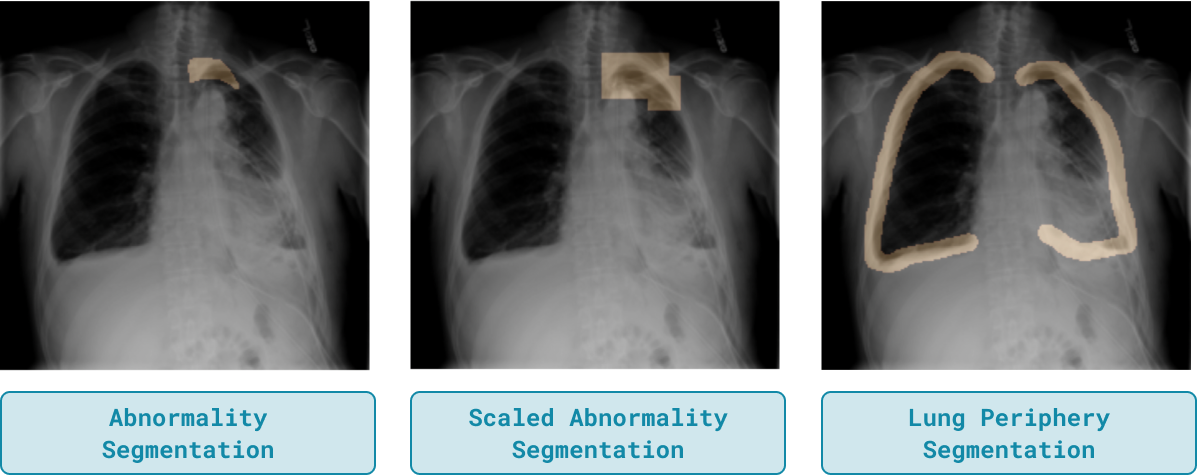

We hypothesize that incorporating these newly curated lung periphery segmentation maps which capture both the abnormality and relevant regions of the background will improve upon the original performance of ActDiff and RRR. In addition, we compare these new segmentation maps to a naive method of obtaining more of the image background by scaling the ground-truth segmentations to a smaller resolution so that they cover a larger area. Figure 2 compares each of these types of segmentation maps for a given image.

We run experiments for both methods with each of the new segmentation maps. Table 2 reports results for ActDiff while results for RRR are in the Appendix. Lung periphery segmentations greatly increase the performance of ActDiff on the target sets, improving upon the ground-truth segmentations by an average of 6.32 points in AUROC. This highlights the effectiveness of including task-relevant regions outside the abnormality mask for OOD generalization.